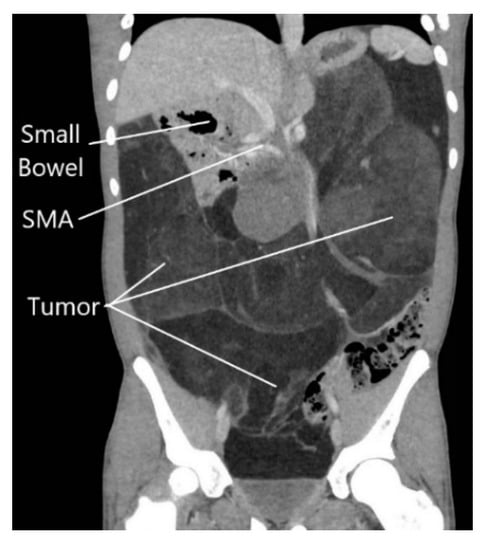

A previously healthy 15-year-old male was referred to our hospital presenting with early satiety, 20 kg weight loss (body mass index = 18.1 kg/m2), and abdominal fullness on exam. Abdominal computed tomography (CT) revealed a massive retroperitoneal tumor shifting the entire small bowel into the right upper quadrant, with significant lateral displacement of the superior mesenteric artery (SMA) from its normal anatomic course (Figure 1). The tumor was compressing all intra-abdominal organs, including the stomach, likely causing his symptoms of early satiety. Percutaneous biopsy of the mass demonstrated a well-differentiated liposarcoma. Chest CT did not show any evidence of lung metastases.

In the present case, the patient’s large intra-abdominal tumor was displacing the entire small bowel to the right upper quadrant, effectively “propping open” the aortomesenteric angle as seen by the perpendicular course of the SMA compared with normal anatomy (Figure 1). The patient’s pre-operative weight loss, coupled with a rapid return of the small bowel mesentery to its normal anatomic position, likely resulted in the observed SMA syndrome. Another unique feature distinguishing this case from other reported post-operative SMA syndrome cases is that apart from an appendectomy, no native anatomic structures were resected or artificially rearranged in an effort to obtain negative surgical margins.

Figure 1. Abdominal computed tomography scan showing massive retroperitoneal liposarcoma, with displacement of the small intestine to the right upper quadrant.